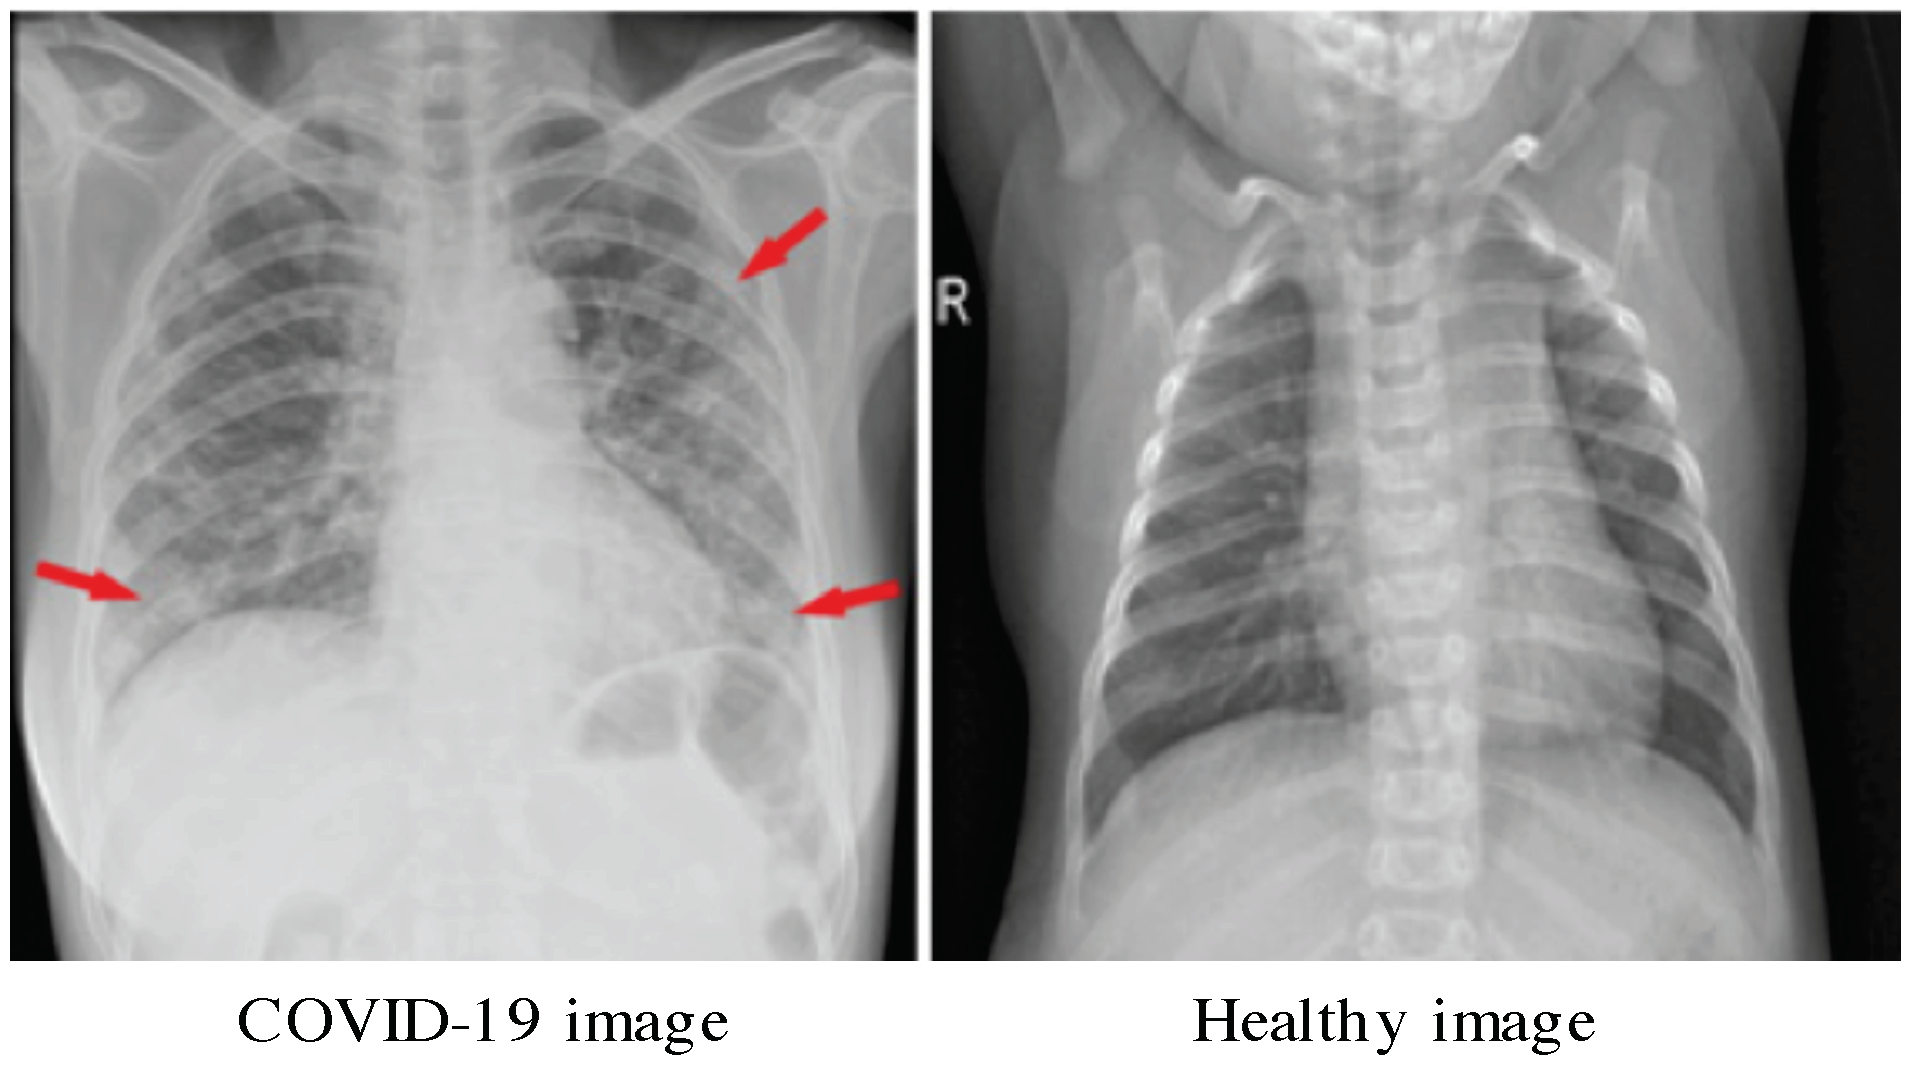

1. Introduction and Related Works

2. Motivations

4.1. Data Sets